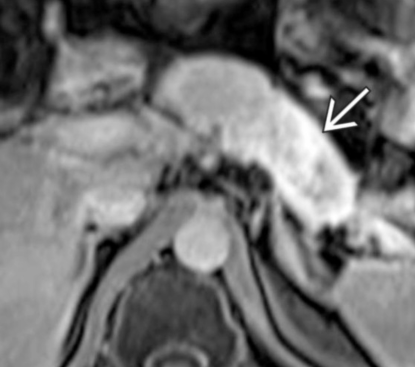

- Infiltration artérielle: <180° vs >180° et cranio-caudalement >2cm vs <2cm

- Infiltration veineuse: Contact, engainement, sténose, occlusion

- Infiltration de la lame rétroporte (entre l’AMS et l’uncus)

Lame rétroporte

Critères de résequabilité